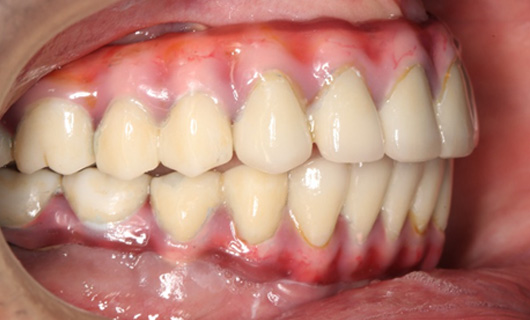

Dentures that are supported by an implant can provide significant improvements in chewing and smiling. In contrast to regular complete dentures, these dentures are horseshoe-shaped reducing bulkiness and creating more space on the palate for better tasting ability. A person with implant-supported dentures can enjoy fruits, vegetables, steaks, corn on the cob, and other foods compared to a person wearing traditional dentures. In addition, implant-support dentures significantly boost patients’ confidence to smile and speak.

- They function like normal teeth

- Significantly improves chewing efficiency resulting in overall well-being.